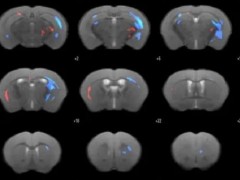

- 南京大学徐运教授︱MFG-E8改善慢性脑缺血相关认知障碍